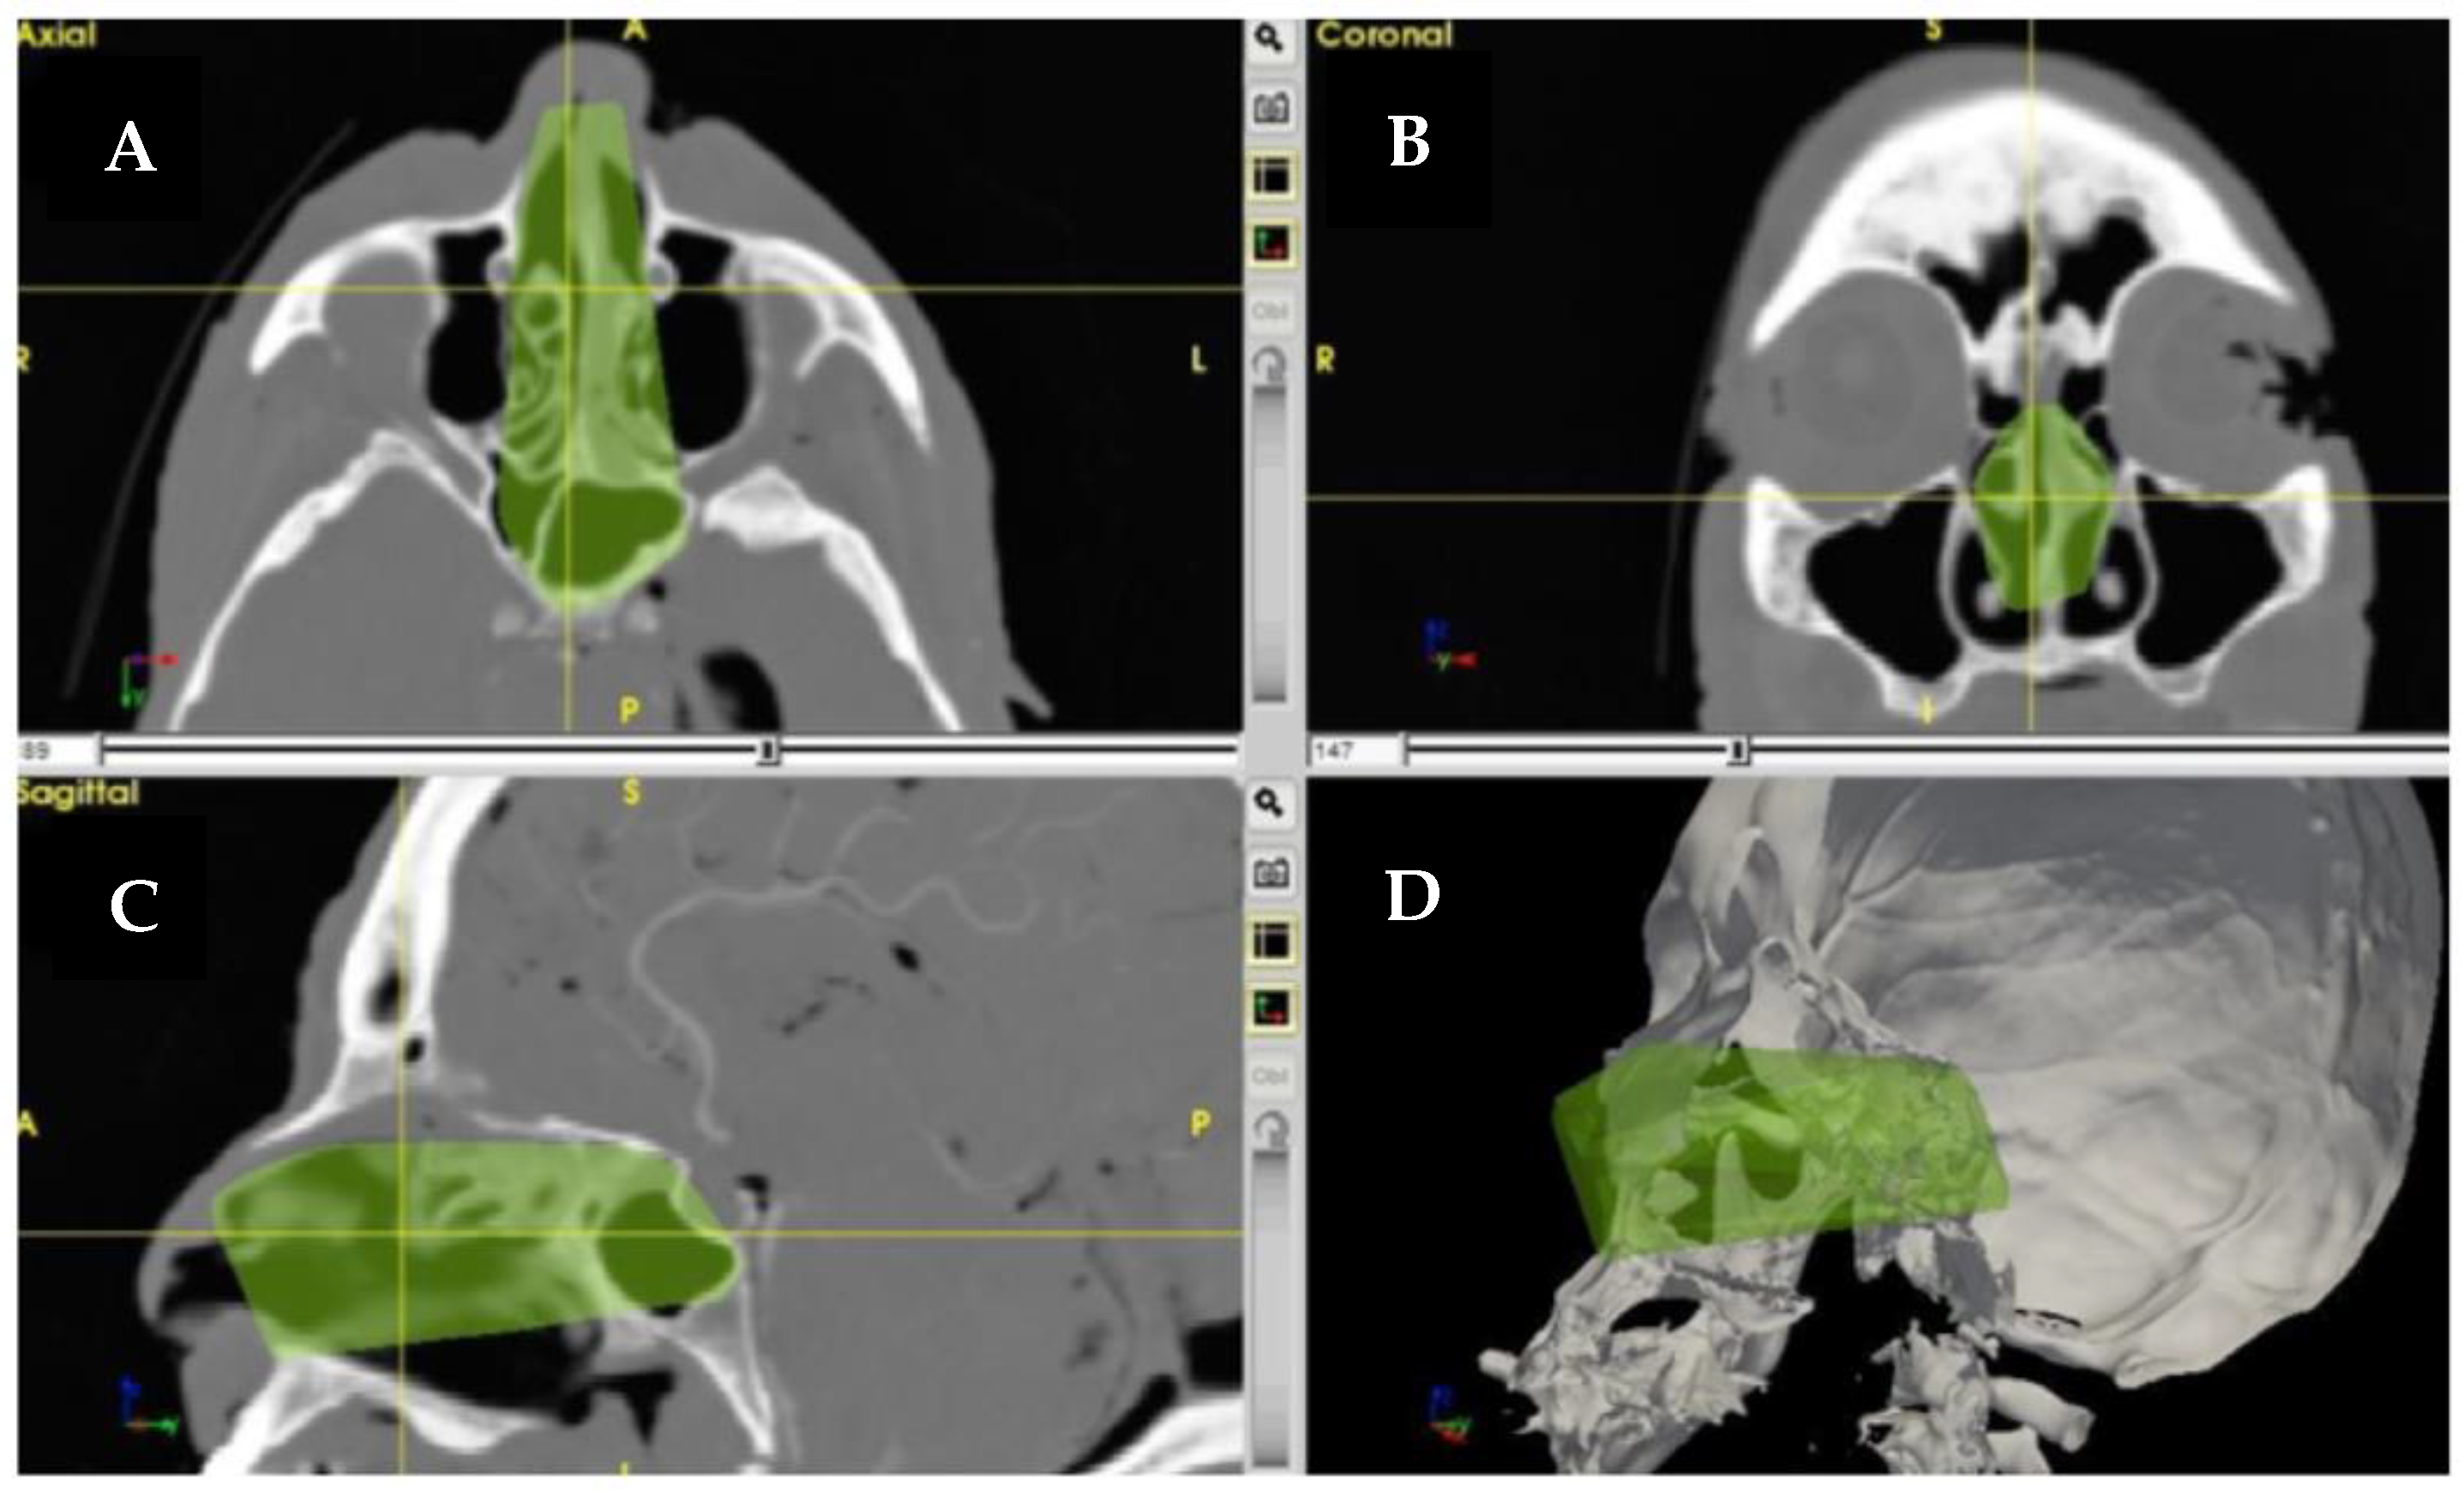

- Taboni, S.; Ferrari, M.; Daly, M.J.; Chan, H.H.L.; Eu, D.; Gualtieri, T.; Jethwa, A.R.; Sahovaler, A.; Sewell, A.; Hasan, W.; et al. Navigation-Guided Transnasal Endoscopic Delineation of the Posterior Margin for Maxillary Sinus Cancers: A Preclinical Study. Front. Oncol. 2021, 11, 4502. [Google Scholar] [CrossRef]

- Sahovaler, A.; Chan, H.H.L.; Gualtieri, T.; Daly, M.; Ferrari, M.; Vannelli, C.; Eu, D.; Manojlovic-Kolarski, M.; Orzell, S.; Taboni, S.; et al. Augmented Reality and Intraoperative Navigation in Sinonasal Malignancies: A Preclinical Study. Front. Oncol. 2021, 11, 4507. [Google Scholar] [CrossRef] [PubMed]